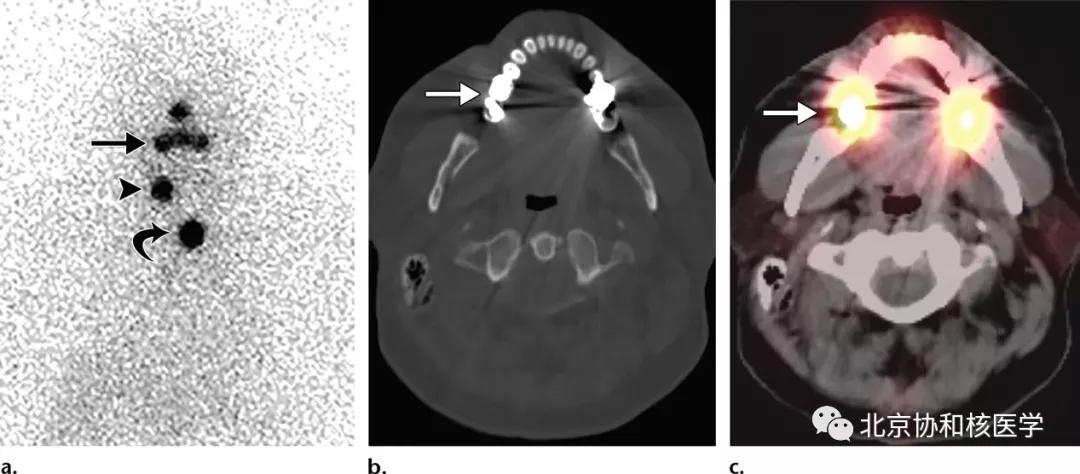

鼻腔脓肿所致碘摄取,其下方可见颈部残余甲状腺:

鼻腔息肉所致碘摄取,同时可见颈部残余甲状腺组织:

鼻骨骨样骨瘤所致碘摄取,腹部另可见由于巨大肾囊肿所致碘异常摄取: